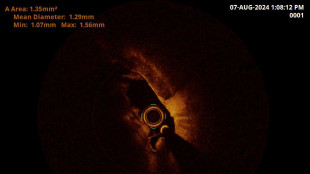

Bimba di un giorno operata a Cosenza da medici di Taormina

Per grave insufficienza respiratoria, intervento medici del Ccpm